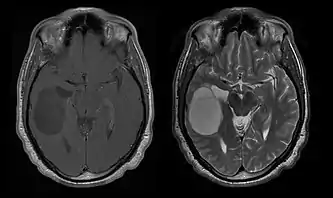

A tomografia computadorizada (TC) e a ressonância magnética (RM) podem detectar efetivamente uma neoplasia no cérebro. A RM é mais sensível que a TC para identificar lesões, mas contraindicações para pacientes com marcapasso cardíaco, próteses incompatíveis, clipes metálicos e outros. A TC continua sendo o método de escolha para detectar calcificações dentro de lesões ou erosões ósseas da calota craniana ou da base. A utilização de agentes de contraste, que são iodados no caso da TC e paramagnéticos ( gadolínio ) no caso da RM, permite a aquisição de informações sobre a vascularização e integridade da barreira hematoencefálica, uma melhor definição do tumor tumoral comparado ao edema circundante e à geração de hipóteses sobre o grau de malignidade . O exame radiológico também permite avaliar os efeitos mecânicos e consequentes alterações nas estruturas cerebrais decorrentes do tumor, como hidrocefalia e hérnias, cujos efeitos podem ser fatais. Finalmente, na preparação para a cirurgia, esse diagnóstico pode ser usado para determinar a localização da lesão ou a infiltração do tumor em áreas vitais do cérebro. Para isso, a RM é mais eficiente que a TC, pois pode fornecer imagens tridimensionais.

As ferramentas de diagnóstico por imagem radiológica destacam a mudança no tecido neoplásico em comparação com o parênquima cerebral normal (através de alterações na densidade do tecido fotografado eletronicamente na TC e na intensidade do sinal na RM). Como a maioria dos tecidos patológicos, os tumores também são reconhecidos por um acúmulo aumentado de água intracelular. Na tomografia computadorizada aparecem hipodensa, ou seja, de menor densidade que o parênquima cerebral, na tomografia de ressonância magnética nuclear com relaxamento spin-lattice T 1 hipointenso e em relaxamento spin-spin T 2 bem como a ponderação de prótons (PD) hiperintensa.

A tomografia computadorizada do cérebro normalmente mostra uma massa de tecido que pode ser realçada por qualquer contraste. Na TC, os gliomas de baixo grau geralmente parecem isodensos ao parênquima normal e, portanto, podem não apresentar realce pelo contraste. Da mesma forma, lesões na fossa posterior do crânio são difíceis de identificar na TC. Consequentemente, os resultados dessa tomografia isoladamente nem sempre são suficientes para fins diagnósticos. Em casos duvidosos, o uso da ressonância magnética mais sensível é essencial.

Na ressonância magnética, um tumor intracraniano aparece como uma lesão maciça que pode se tornar mais luminescente após o uso do agente de contraste. No entanto, há sempre uma anomalia de sinal na ressonância magnética, que indica a presença de neoplasia ou edema vasogênico. Normalmente, o aumento da luminescência (realce pelo contraste) é indicativo de um tumor de grau mais alto de malignidade. Um anel contrastante é característico do glioblastoma, com a porção luminescente correspondendo à parte vital do tumor maligno e a área mais escura-hipointense à necrose tecidual.